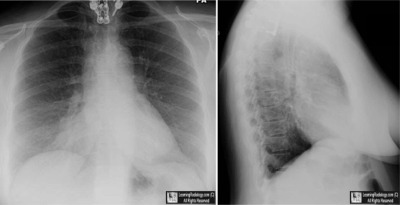

• 51 year-old with chest pain

Frontal and Lateral Chest Radiographs

3. Epicardial Fat Pad

Epicardial Fat Pad

• An accumulation of fat between the parietal pericardium and the parietal pleura, usually found incidentally on chest radiography

• Most common in either the right cardiophrenic angle or adherent to the left ventricle at the apex of the heart

• On the left side, it blunts the normal rounded apex of the heart

• Can be mistaken for pneumonia or a mass